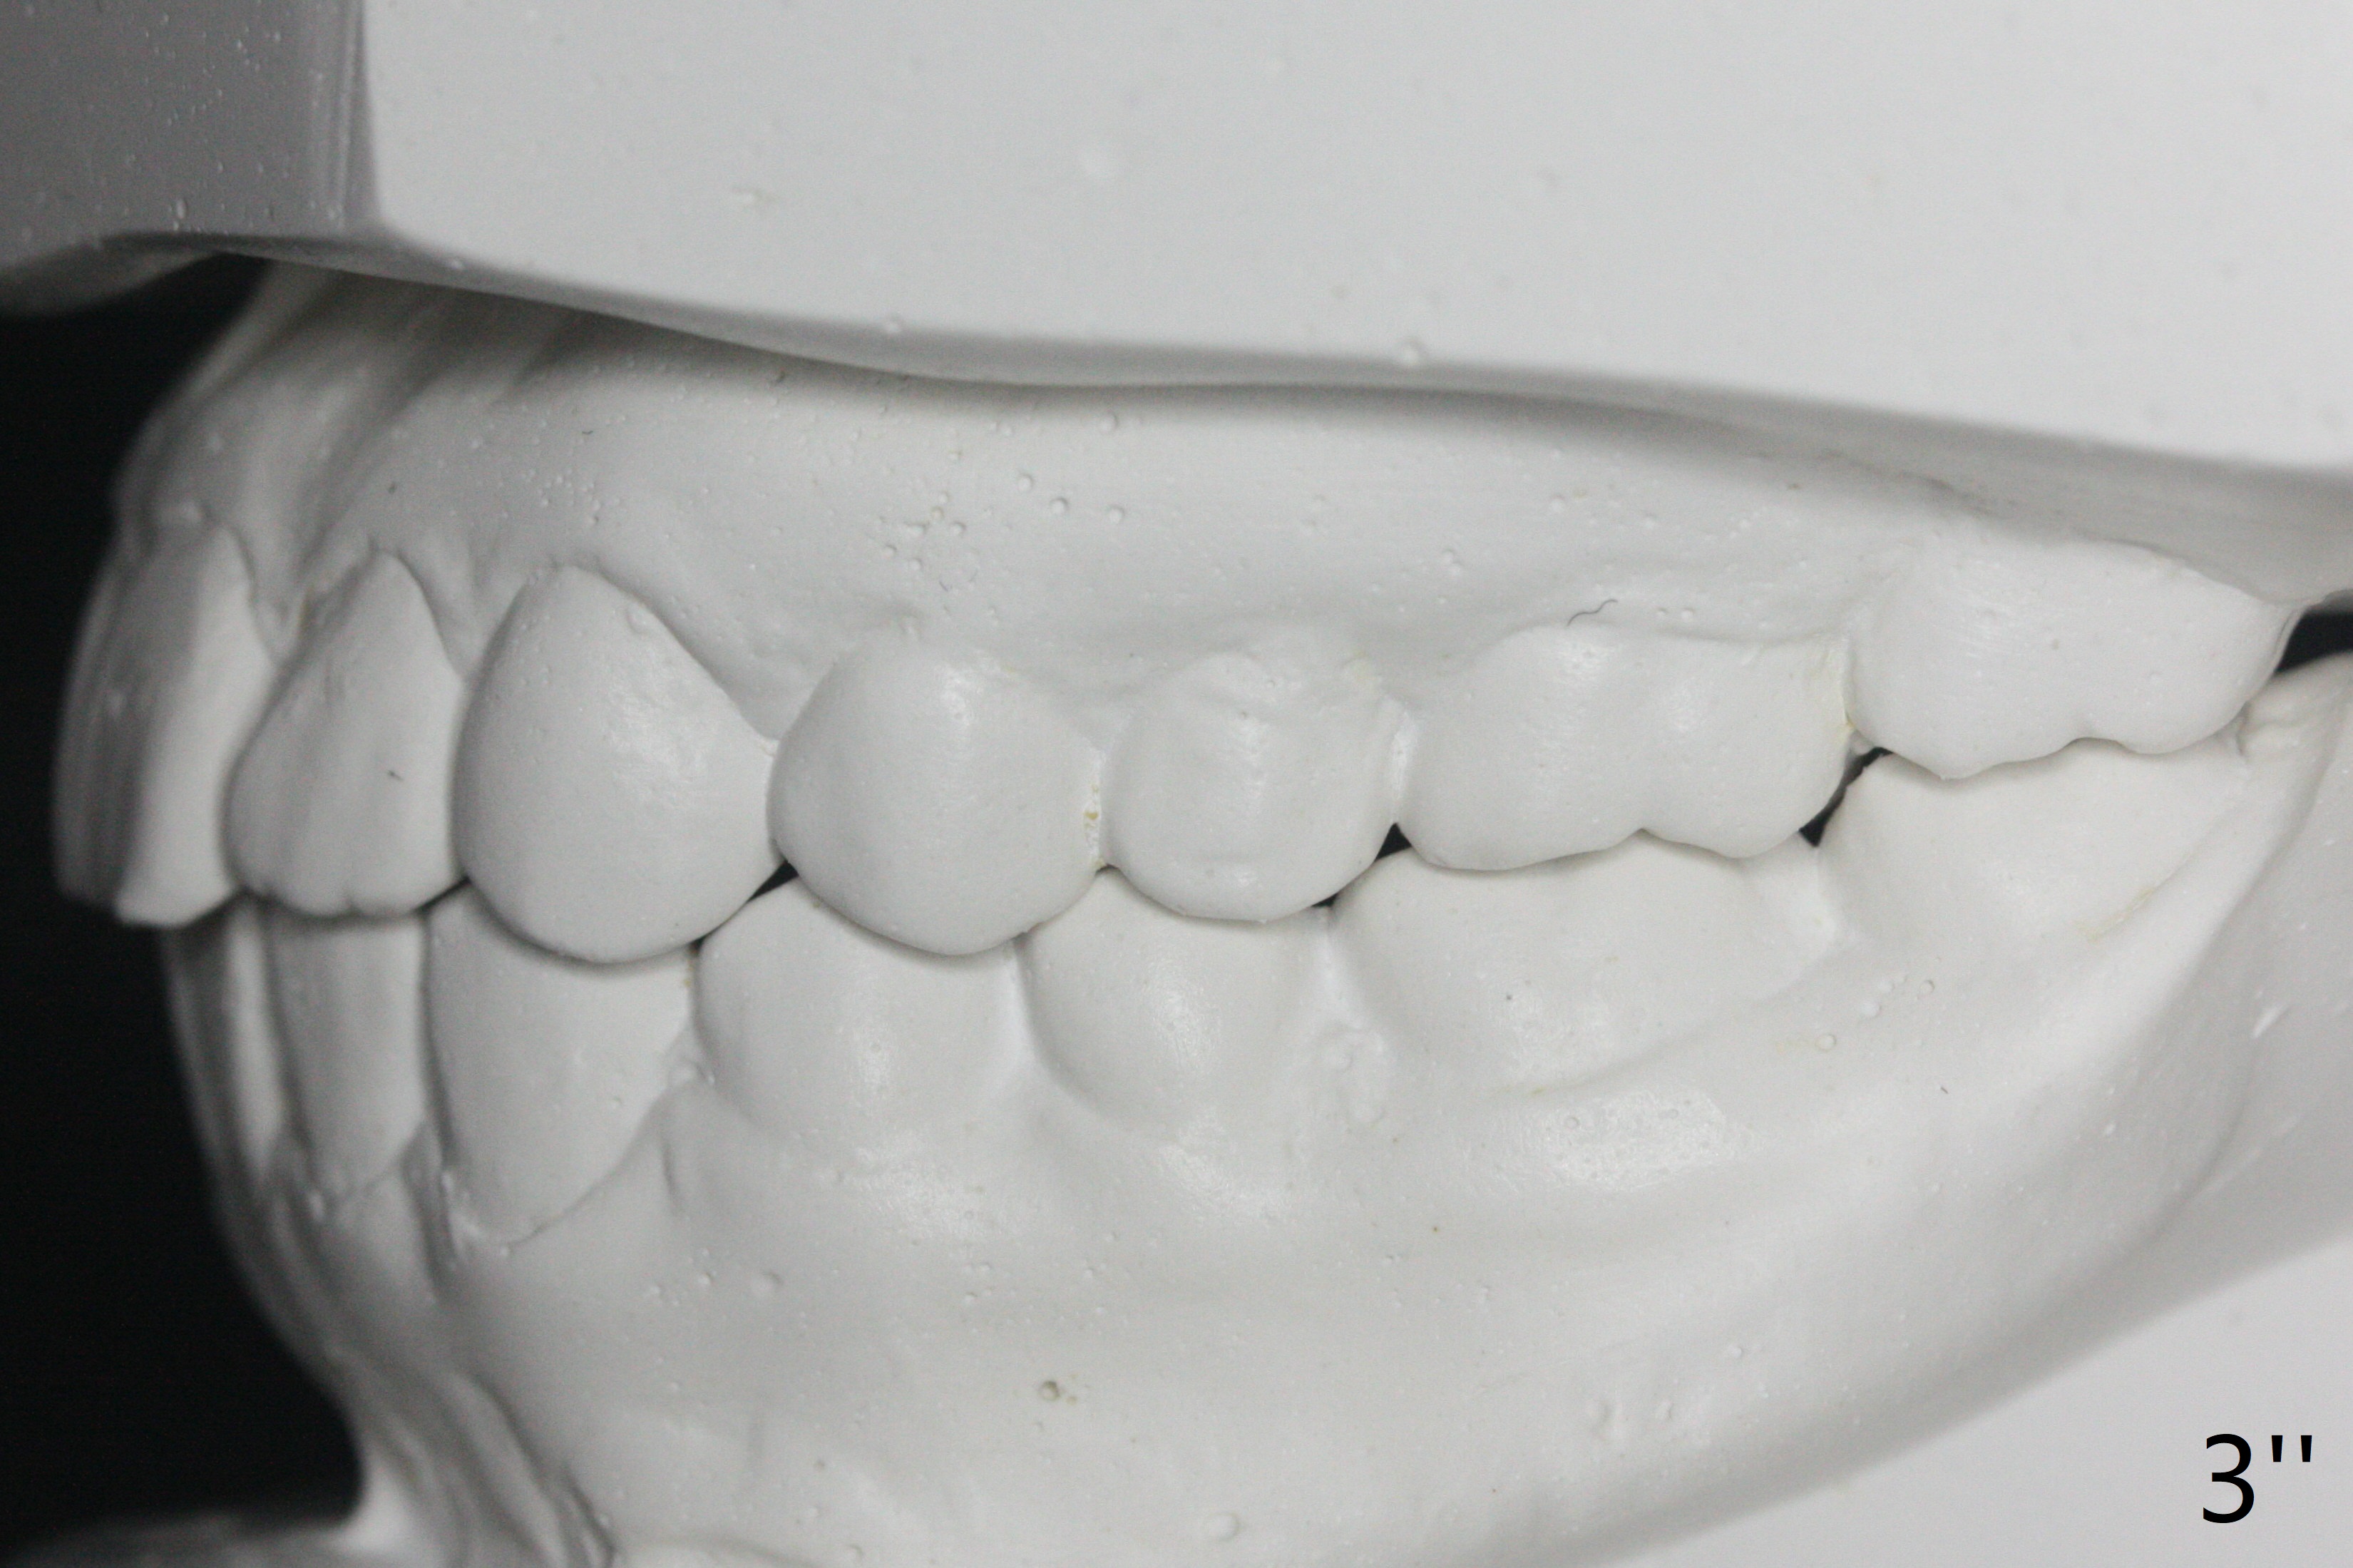

A 12-year-old woman has severe crowding including UL7 impaction (Fig.1-5), finishes non-extraction orthodontics at the age of 15 (Fig.1'-5') and returns for retainer remake at 19 (Fig.1''-5''). Four years post debanding, UL7 (Fig.4') seems to improve its position (Fig.4'').